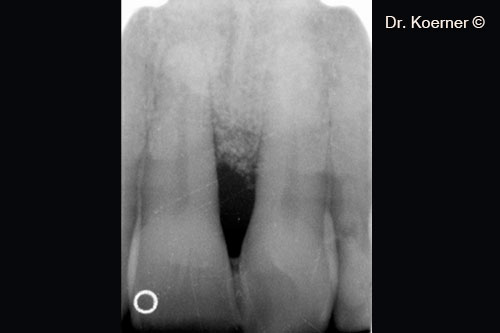

Initial x-ray